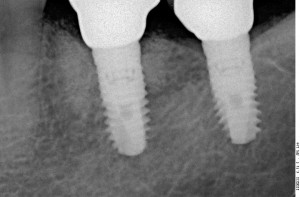

Прицельный радиовизиографический снимок можно сделать в любой из наших клиник. В отличие от обычных прицельных рентгенограмм зубов, доза лучевой нагрузки при проведении подобного исследования в несколько раз ниже, поэтому таких снимков можно сделать очень много. Например, по существующим стандартам, терапевт стоматолог может сделать до десяти снимком зуба в процессе эндодонтического лечения — и это, разумеется, необходимо для качественного лечения каналов зубов.

В хирургической практике я использую прицельные снимки как для первичной диагностики: например, чтобы быстро понять локализацию ретинированного зуба мудрости и его отношение к окружающим структурам, либо для интра- и послеоперационного контроля результатов имплантологического лечения. А наличие цифровой базы радиовизиографических снимков позволяет понять, как ведет себя протез на импланте в течение длительного времени: